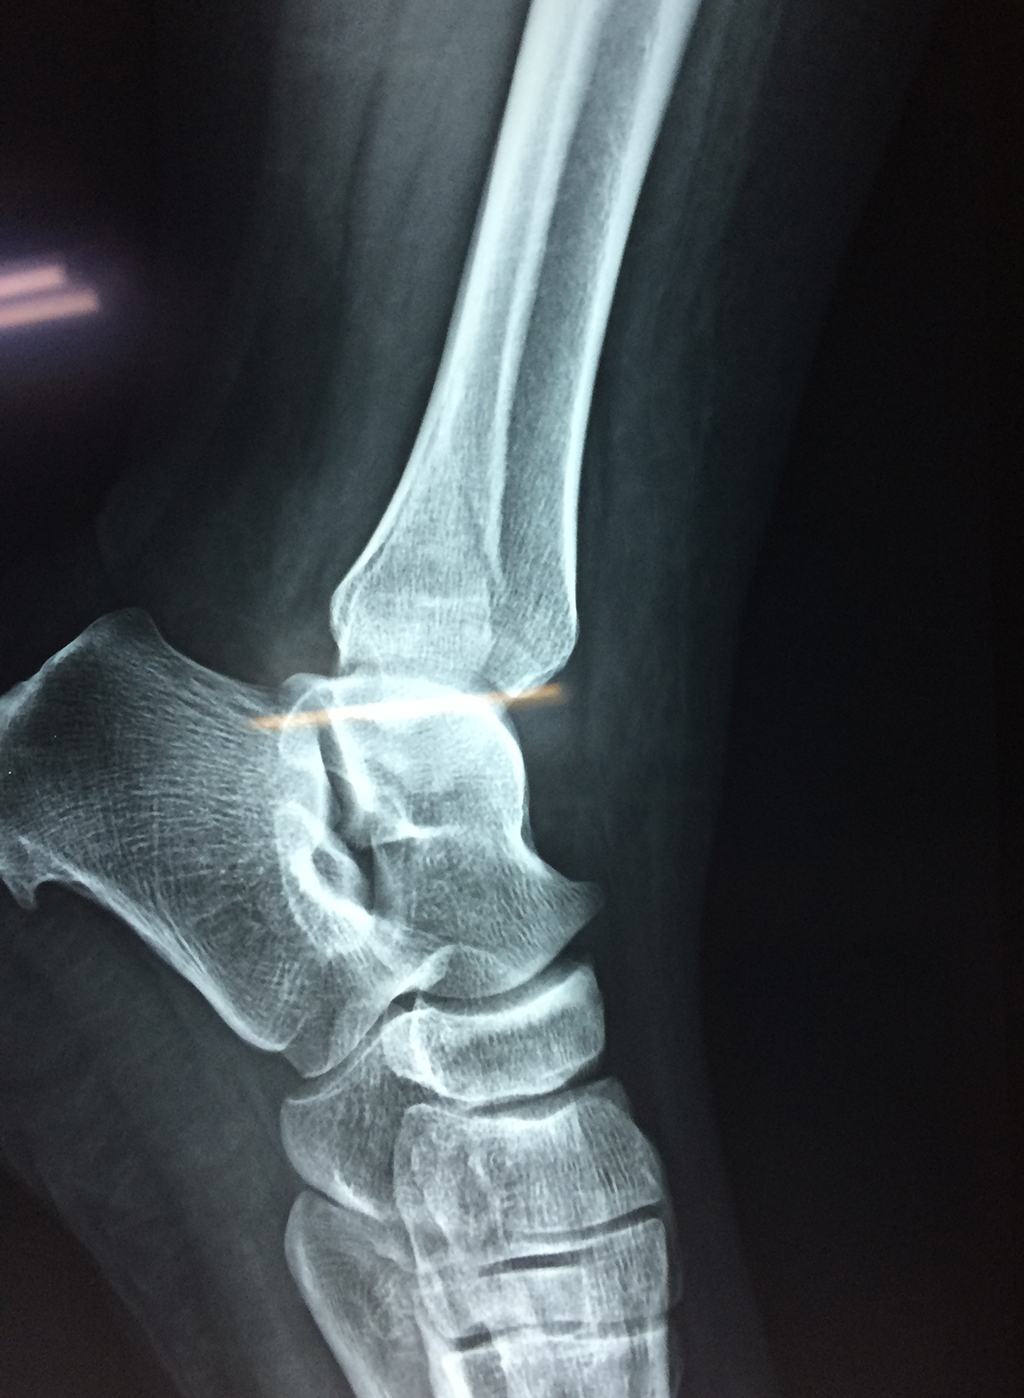

Algunas fracturas de tobillo pueden requerir cirugía si:

- Los extremos de los huesos están desalineados entre sí (desplazados).

- La fractura se extiende hasta la articulación del tobillo (fractura intra-articular).

- Los tendones o ligamentos (tejidos que sujetan los músculos y los huesos entre sí) están rotos.

Cuando se necesita cirugía, es probable que esta implique el uso de clavijas de metal, tornillos o placas para sostener los huesos en su lugar mientras la fractura se consolida. Los elementos de soporte pueden ser temporales o permanentes.